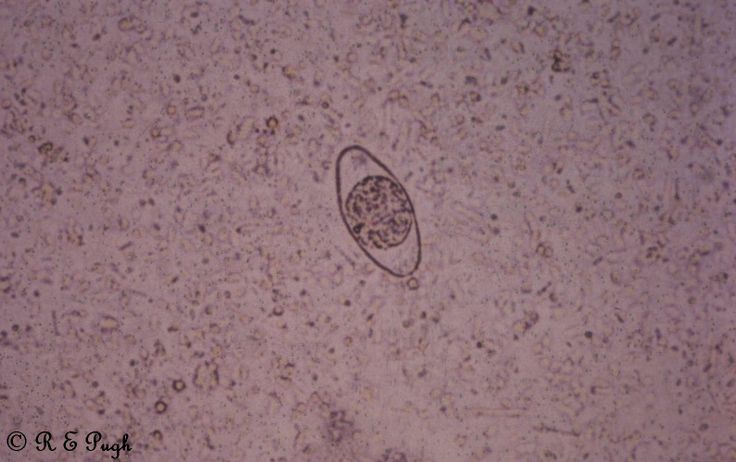

Наиболее часто встречающиеся у домашних птиц кокцидий принадлежат к роду Eimera. Виды Eimeria часто отличаются морфологией ооцисты, которая представляет собой толстостенную зиготу, распространяющуюся с пометом зараженного хозяина. Ооцисты заключены в толстую наружную оболочку и состоят из единственной клетки, запускающей процесс споруляции, в результате которого примерно через восемь часов образуются инвазивные ооцисты (рис.).

У видов Eimeria прямой цикл развития (рис. 1). Спорулированные ооцисты («яйца» паразитов) проникают в организм цыплят из инфицированного помета, после чего попадают в пищеварительный тракт, где паразиты проникают в клетки стенки кишечника.

Проходит несколько фаз развития, после которых образуются ооцисты, выводящиеся из организма с пометом. В зависимости от окружающих условий (в том числе температуры и влажности) ооцисты спорулируют и становятся заразны. Весь цикл занимает от 4 до 6 дней. Этот короткий прямой жизненный цикл в сочетании с потенциалом к массовой репликации на внутриклеточной стадии делает данную группу паразитов серьезной проблемой в условиях интенсивного птицеводства.